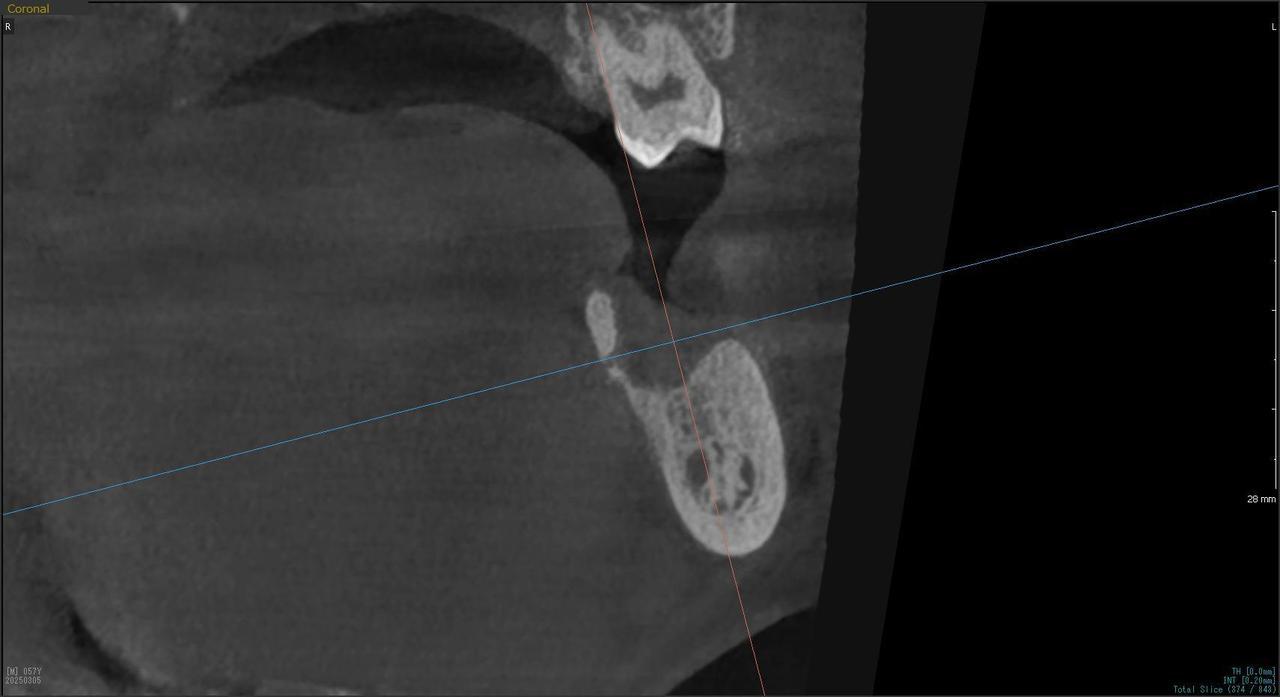

4.右上5が折れたために、インプラント抜歯即時埋入をおこなったインプラント治療のケース。

Before

枚方市のインプラントの症例

T・T 様 女性 40代

症状としては、 右上5番の歯が折れてしまった。保存することは不可能な状態であった

治療法としては、患者様は、歯が折れたことを主訴に来院。インプラント治療を希望したため、抜歯した当日に、インプラント埋入をおこなって、骨欠損部には人工骨を補填した。1か月半後にインプラントが骨と結合していることを確認できたため、光学印象を行い、2か月後に、最終補綴物として、アバットメントとジルコニアクラウンの装着を行いました。

治療結果としては、抜歯したと同時にインプラントを埋入することで、抜歯した穴が自然に治る過程で、インプラントの骨結合と組織の治癒が同時に行われるために、2か月という治療期間で治療を終了することができたことと、機能面・審美面でも回復を行うができた。

治療の期間・回数:約2か月、インプラント抜歯即時埋入から最終補綴物装着まで4回

治療の価格:352,000円(税込)

治療費の内訳:インプラント基本料(フィックスチャー及び手術費用、投薬費用、レントゲン費用、インプラント上部費用(アバットメントおよびジルコニアクラウンの費用用)330000円(税込み)。オプション、抜歯即時埋入加算(人工骨費用を含む) 22000円(税込み)

治療のリスクや副作用:手術後に、痛みや腫れ、出血、合併症などを引き起こす可能性があります。噛む感覚がご自身の歯と異なる場合があります。見た目がご自身の歯と異なる場合があります。手術後にメインテナンスを継続しないと、インプラントが抜け落ちる可能性があります。